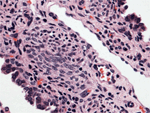

The histopathology examination showed hypercellular foci composed of primitive spindled and round cells.

![]() Figure 12 |

The above findings were consistent with the diagnosis of pleuropulmonary blastoma type I.